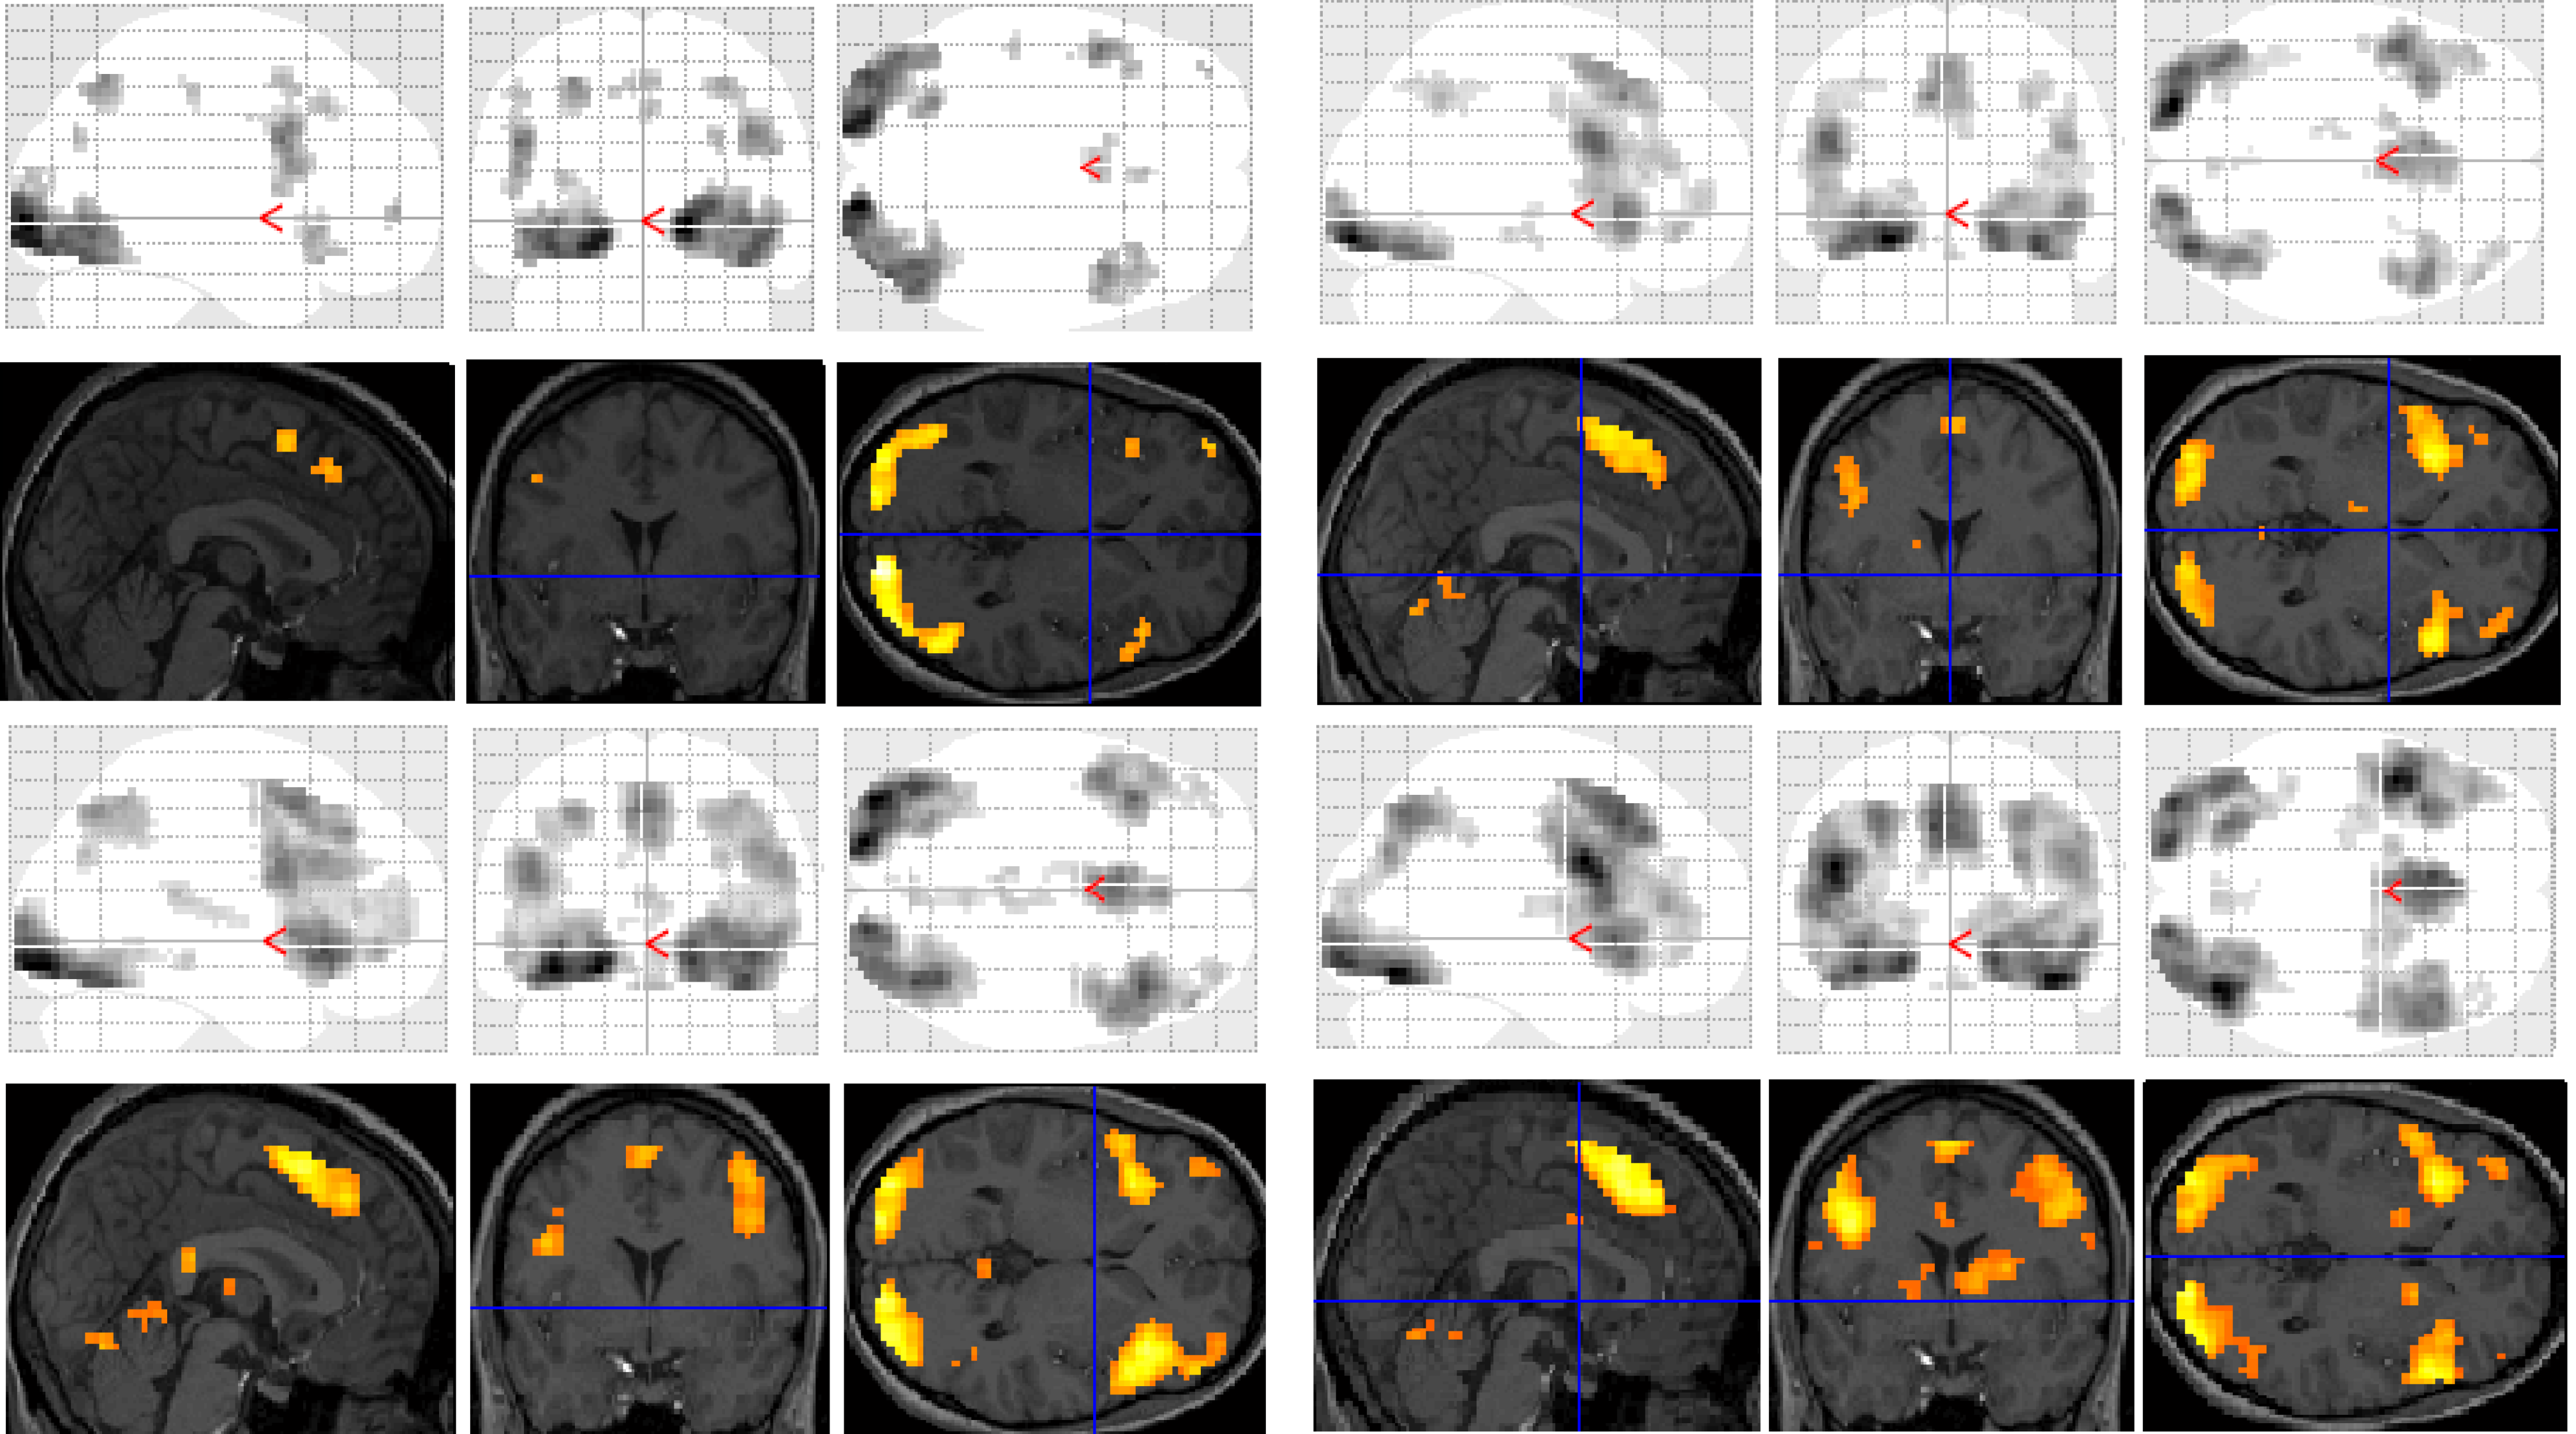

Functional MRI results for each of the subjects were analysed and organised according to the contrast of interest (versus baseline fixation): (1) letter case judgment; (2) regular word decision; (3) irregular word decision; (4) pseudoword decision. Significant clusters of activation for each contrast on section overlay and glass brain statistical parametric maps (SPMs) are illustrated separately for control (Figure 1) and dyslexic (Figure 2) participants.

Figure 1. Significant clusters of activation displayed on section overlay and glass brain statistical parametric maps (SPMs) observed in control participants for each task contrast (versus baseline fixation): letter case judgment (top left); regular word decision (top right); irregular word decision (bottom left); pseudoword decision (bottom right).